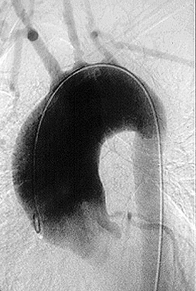

3. Arteritis de Takayasu

1. Pacientes jóvenes

1. Afectación

1. Subclavia

1. Carótida común

1. Aorta abdominal

1. Arteria renal

1. Cayado y raíz de la aorta